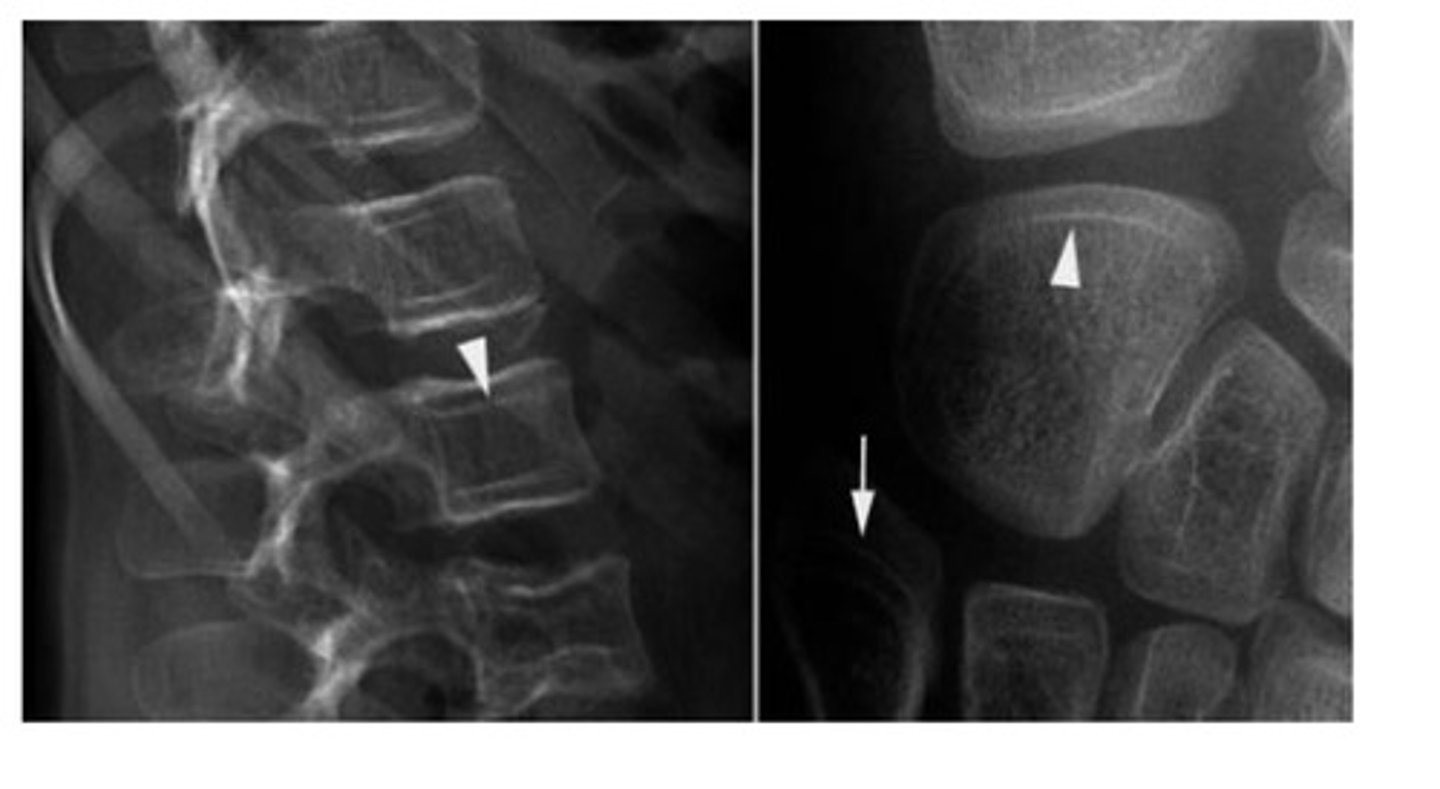

Congenital fusion of ≥2 cervical vertebrae

Idiopathicl: 1/40,000

What type of Congenital Kyphosis

Is worse?

Type 1

What are some characteristics of congenital kyphosis?

Failed development

- severe

- deformity

- possible cord compression

What are some characteristic of type 2 congenital kyphosis?

Failed segmentation (Type II)

• Mild compared to type I

• Mild Deformity

Surgical fusion